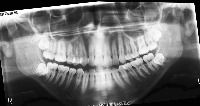

downloadClasses (32)

tooth_11

tooth_12

tooth_13

tooth_14

tooth_15

tooth_16

tooth_17

tooth_18

tooth_21

tooth_22

tooth_23

tooth_24

tooth_25

tooth_26

tooth_27

tooth_28

tooth_31

tooth_32

tooth_33

tooth_34

tooth_35

tooth_36

tooth_37

tooth_38

tooth_41

tooth_42

tooth_43

tooth_44

tooth_45

tooth_46

tooth_47

tooth_48